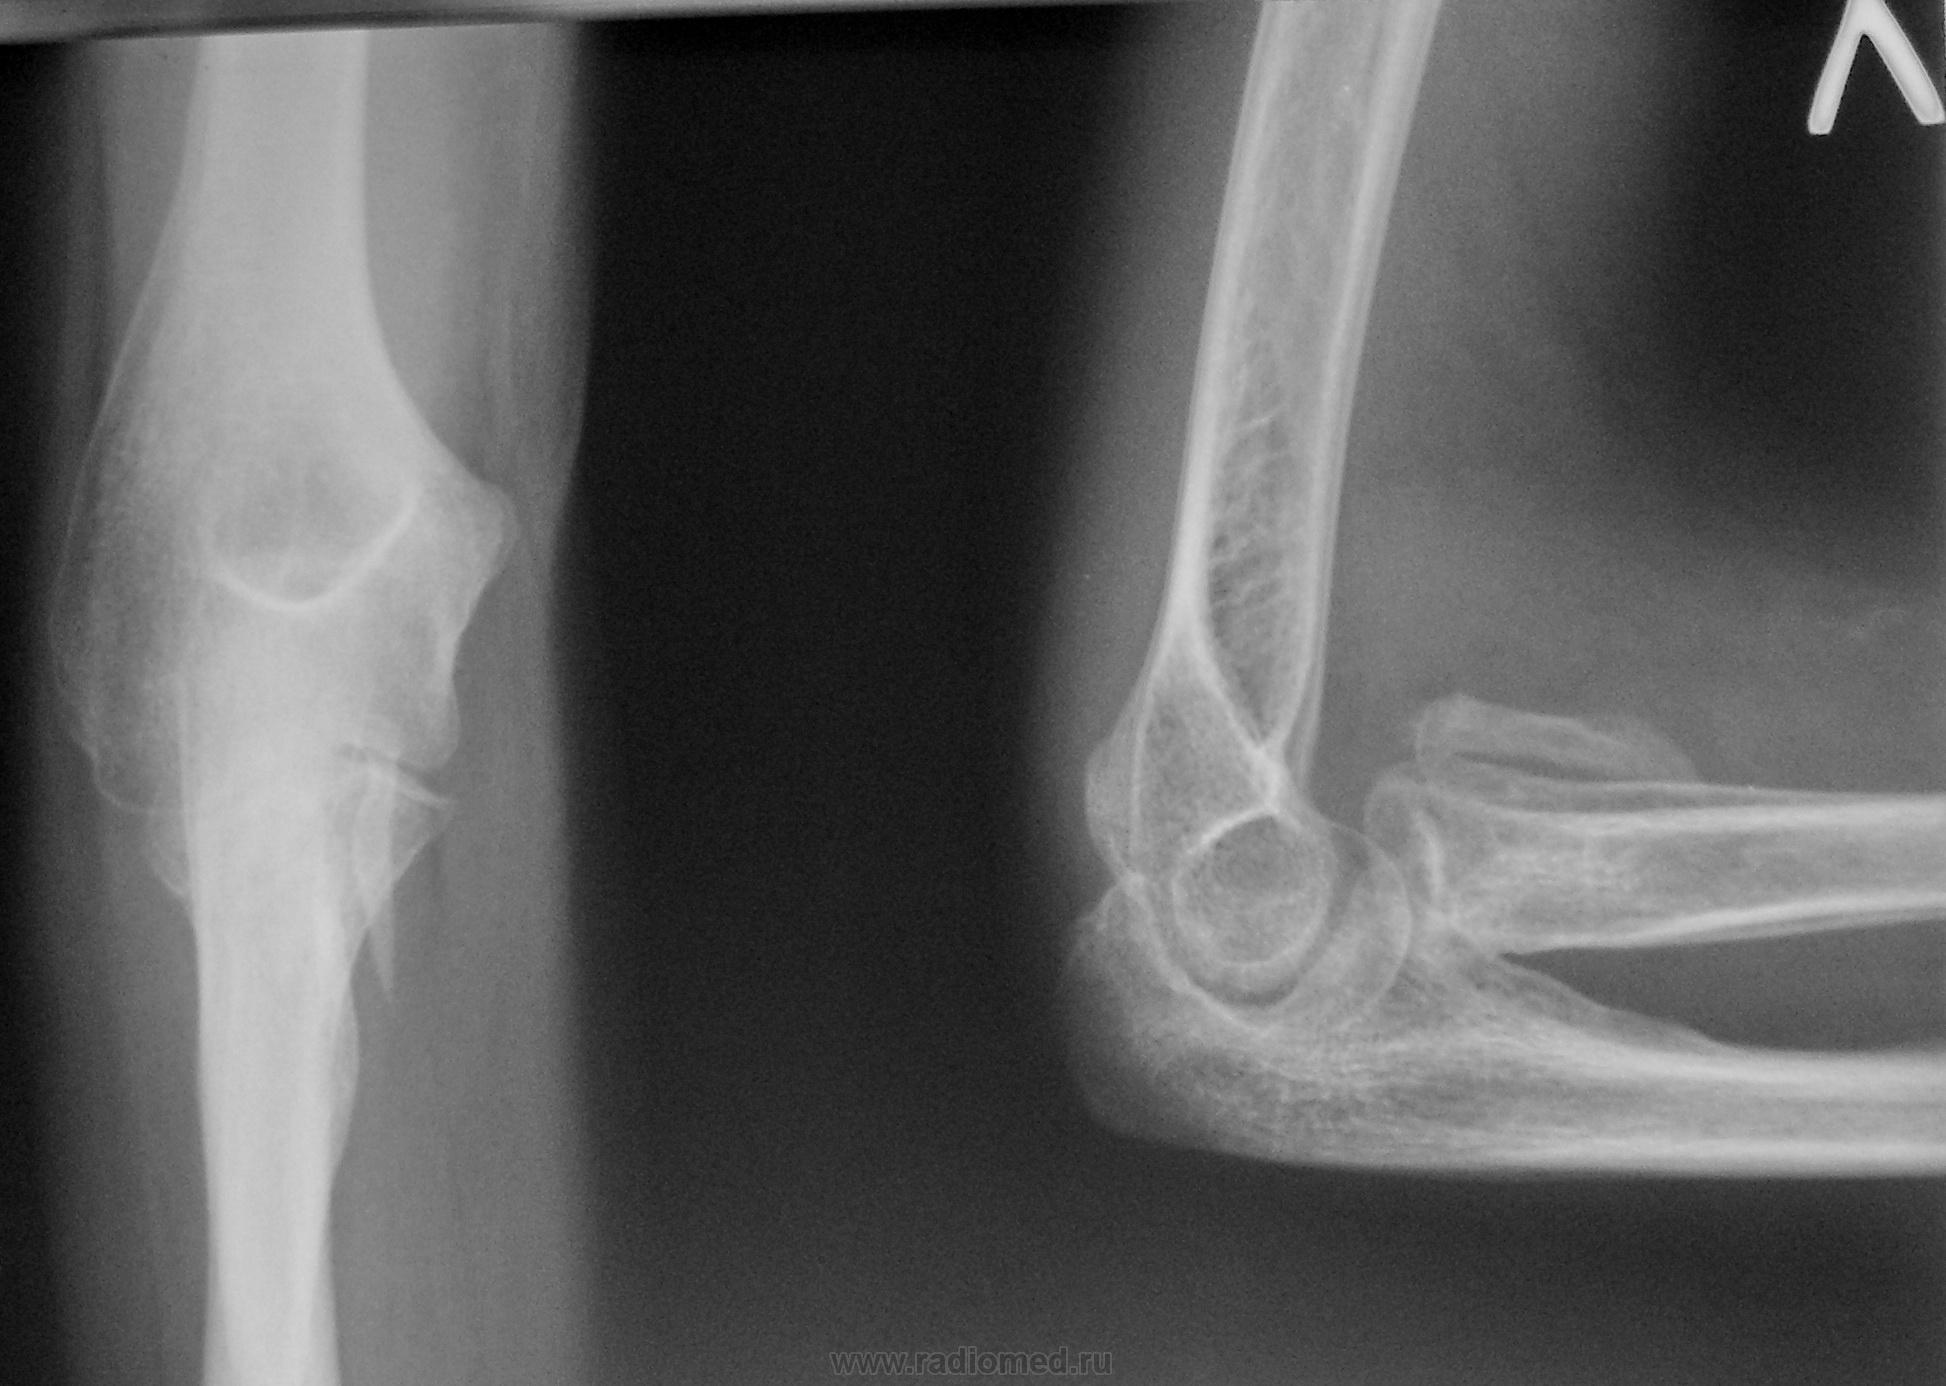

Мальчик, 8 лет, около полугода назад сломал головку луча. Был сделан остеосинтез метал. спицами. Сейчас пришёл на разработку. Но сустав болит и плохо сгибается.

похоже на то, что не устранен вывих головки лучевой кости. а можно архив?

На мой взгляд, откол - костный фрагмент отдельно лежыщий четко визуализируется.

Контрактура видимо. А снимочки после остеосинтеза есть?

А прямой снимок - точно в положении супинации? Отдельно лежит, скорее всего, обызвествившаяся гематома. Ну, и рентгенархив (на руках у пациента), да еще и с выпиской из и/б-ни, прояснили бы ситуацию.

Типичный гетеротопический оссификат, периодически видим такие в локтевых суставах после переломов.

У Рейнберга подобное описывается как оссифицирующий миозит, что наверно является синонимом того, о чём говорит уважаемая Ola-la.